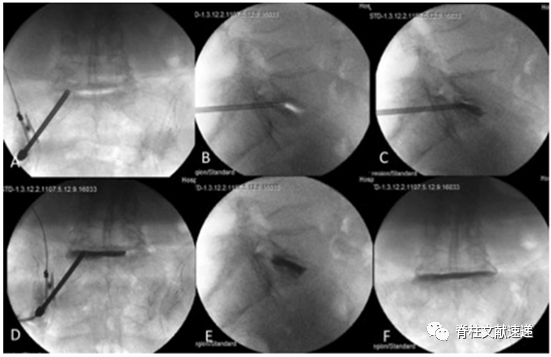

图注:椎弓根外侧入路;A和B:正位和斜位透视下将导针放置于横突和上关节突的交叉处;C:侧位透视下可观察椎间盘内导针的深度;D:C臂透视下缓慢注入骨水泥;

图注:经椎弓根入路;A和B:L5/S1节段通过S1椎弓根入路穿刺,穿透L5上终板至L5/S1椎间隙;C和D:缓慢注入骨水泥,注意观察是否发生骨水泥渗漏;E和F:术后正侧位透视结果;